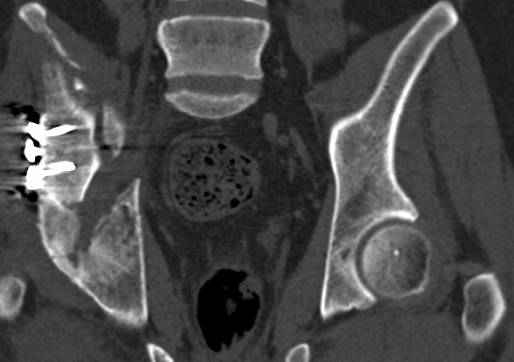

высылаю дополнительно сканы.

итак, второй вариант: высокий двухколонный с вовлечением КПС... Ни одно из основных повреждений не репонировано, кроме задней стенки. Скорее всего попытка реконструкции вертлуги сейчас будет очень травматичной и не очень эфективной, т.е. вероятный риск более значим, чем ожидаемая польза... Лучше подождать, и потом сразу эндопротез